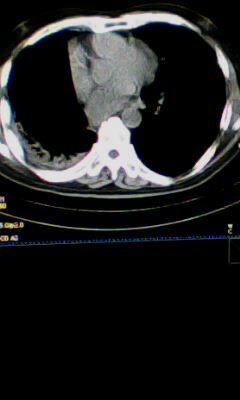

标题: CT25675:男 71 肺癌部分切除术后 3年 [打印本页]

标题: CT25675:男 71 肺癌部分切除术后 3年

右肺癌切除术后。

右肺炎症,左肺炎症。

右侧胸膜肥厚。

1.右肺符合肿瘤切除术后ct表现。

2.左肺炎症。